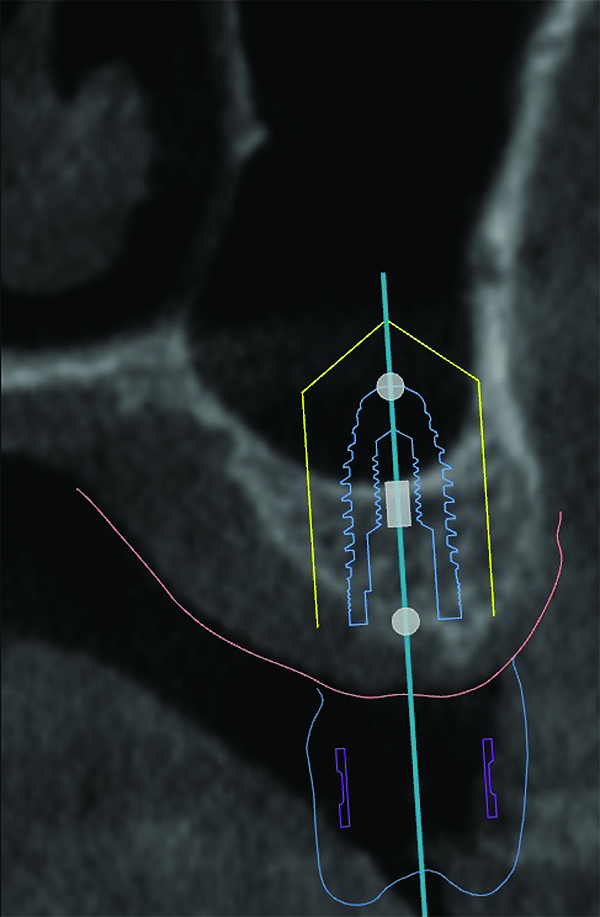

3D radiographic scans obtained using the single scan protocol can be combined with digital mock-ups performed on intraoral optical scans or scans of casts,20 using the existing natural teeth as fiduciary markers. Different masks for bone, teeth, gingiva, and implants can be designated and processed (Figure 13 and Figure 14). This technology allows for greater accuracy, since implant position will be determined based on natural teeth (fiduciary markers) that are likely to be more stable and accurate than fiduciary markers placed on a radiographic guide.

(13) An optical scan of patient’s teeth and diagnostic wax-up was combined with CBCT to facilitate treatment planning of implant placement. Note that there is a need for sinus augmentation to accommodate a dental implant on the right image (blue: tooth contours determined from wax-up/optical impression, red: soft tissue outline).

Figure 13

(14) An optical scan of patient’s teeth and diagnostic wax-up was combined with CBCT to facilitate treatment planning of implant placement. Note that there is a need for sinus augmentation to accommodate a dental implant on the right image (blue: tooth contours determined from wax-up/optical impression, red: soft tissue outline).

Figure 14